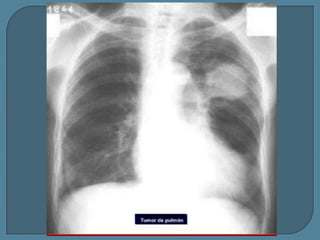

Radiografía simple (A) y TC (B) muestran una gran

masa maligna que mide más de 3 cm.